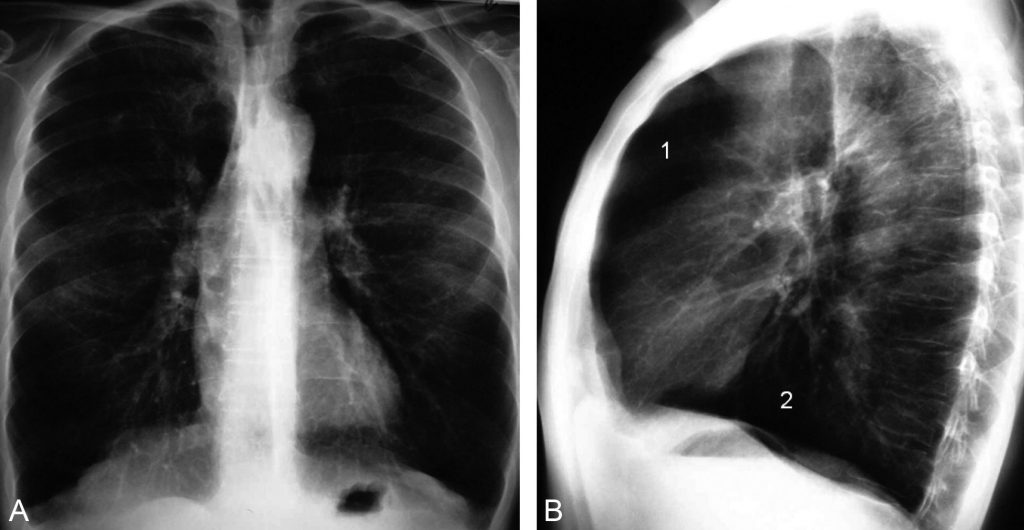

Le cliché radiographique de profil est plus sensible que le cliché de face pour rechercher les signes de distension (figure 90.1) :

Fig. 90.1. Radiographie thoracique de face et de profil.

Le cliché de face (A) montre huit arcs antérieurs de côtes au-dessus du diaphragme et une hyperclarté diffuse du parenchyme pulmonaire. Le cliché de profil (B) montre une augmentation du diamètre antéropostérieur du thorax, un aplatissement des coupoles diaphragmatiques, et un élargissement des espaces clairs rétrosternal (1) et rétrocardiaque (2).

Source : CERF, CNEBMN, 2022.

- aplatissement des coupoles diaphragmatiques ;

- augmentation des espaces clairs rétrosternal et rétrocardiaque ;

- augmentation du diamètre thoracique antéropostérieur (thorax en « tonneau »).

La radiographie de face peut montrer la distension thoracique sous la forme d’une hyperclarté pulmonaire ou la visibilité de plus de sept arcs costaux antérieurs au-dessus du diaphragme.